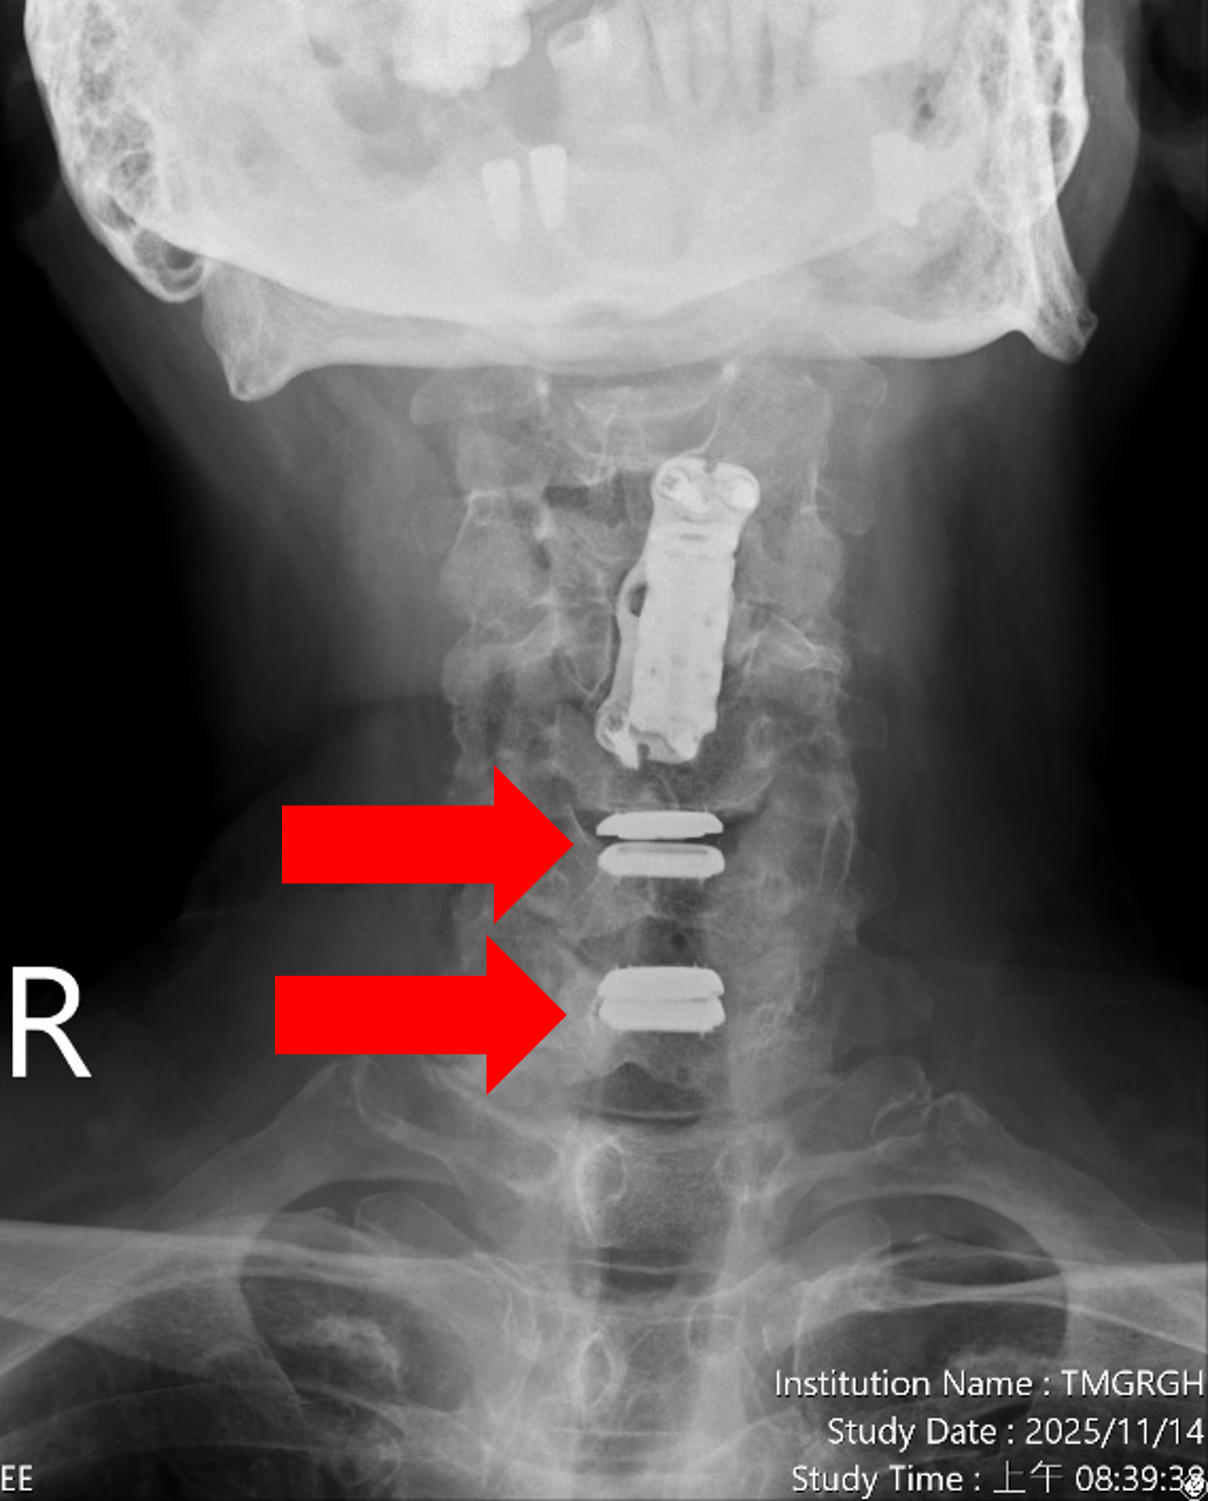

圖一、【治療前】患者曾於年初接受其他醫療院所執行第四頸椎體切除,籠狀支架融合(如左圖紅色箭頭)及第三第五頸椎骨釘骨板固定手術(如右圖藍色箭頭),並有第五第六及第六第七頸椎間盤退化及狹窄情況(如右圖綠色箭頭)。

圖四、【治療後】患者的第五第六及第六第七頸椎間盤切除,並植入人工椎間盤,患者術後症狀解除,不需戴頸圈,一個星期就能回工作崗位。